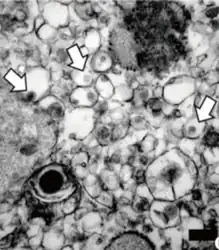

Electron micrograph of "Zika virus". Virus particles (digitally colored purple) are 40 nm in diameter, with an outer envelope and a dense inner core.

Electron micrograph of Zika virus. Virus particles (digitally colored purple) are 40 nm in diameter, with an outer envelope and a dense inner core.[1]